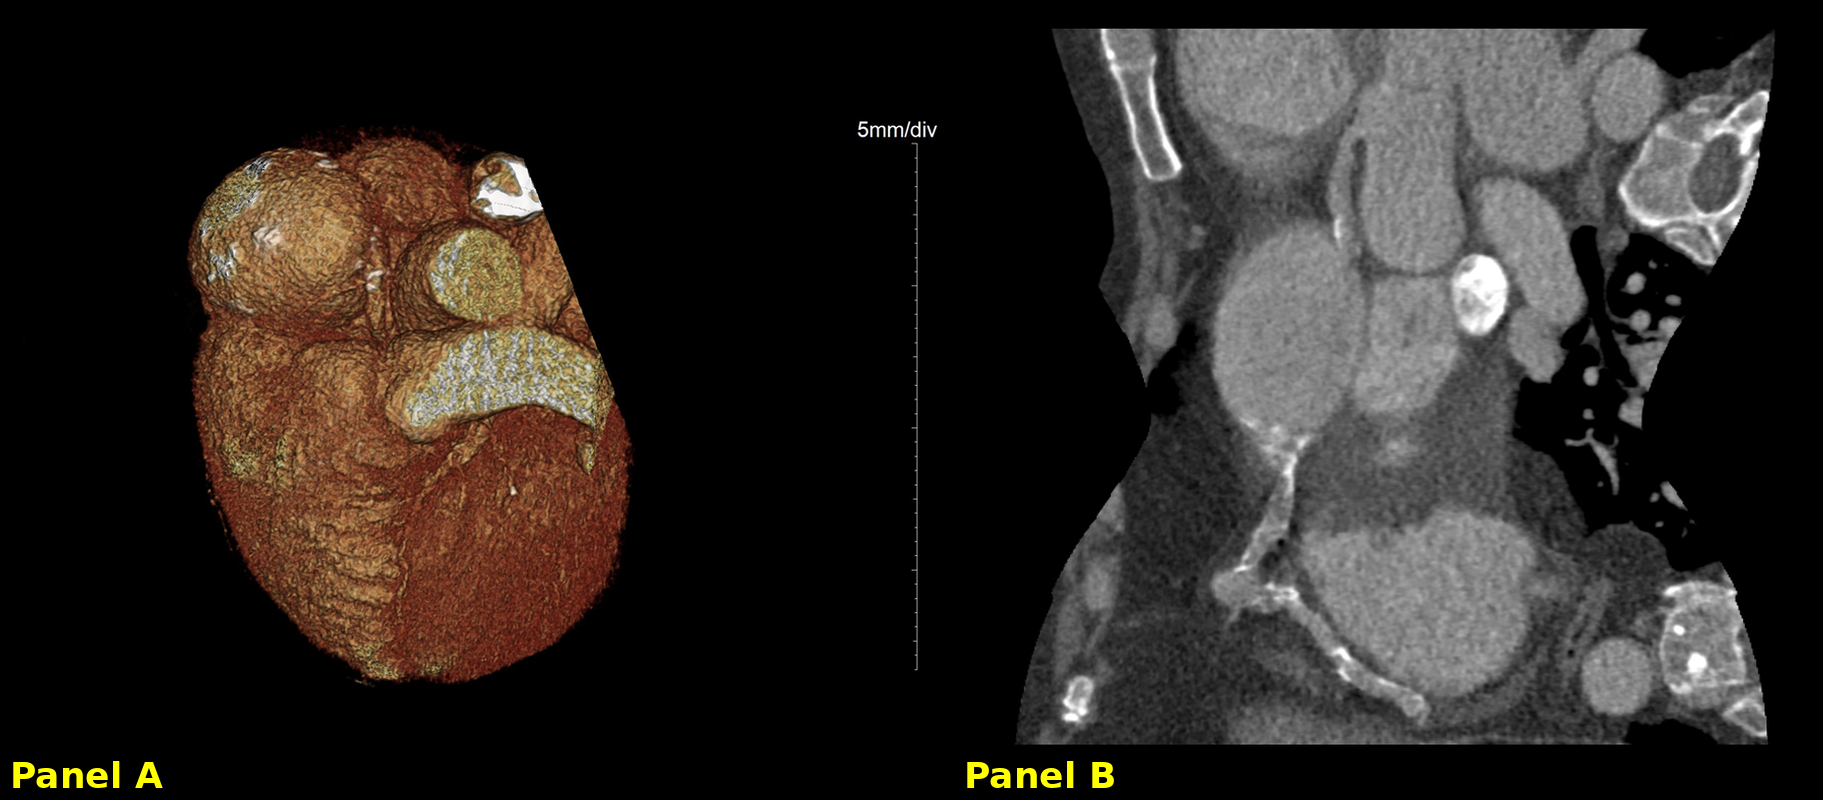

We report a 59-year-old man with prior inferior ST-elevation myocardial infarction (2009) and known right coronary artery (RCA) ectasia, presenting with dyspnea at rest and new-onset atrial fibrillation. Physical examination revealed hypoxemia, bilateral lower extremity edema, and bibasilar crackles. Transthoracic echocardiography showed mild biventricular dysfunction and biatrial enlargement. Pulmonary computed tomography angiography excluded thromboembolism but incidentally identified a 6.6 × 6.4 cm proximal RCA aneurysm. Coronary computed tomography confirmed RA compression without tamponade or restrictive physiology. Right heart catheterization showed normal pulmonary artery pressures, excluding pulmonary hypertension.

Selective RCA catheterization was achieved, and a 0.014-inch guidewire was advanced into the aneurysmal sac. Balloon occlusion was performed proximal to the aneurysm to test for tolerance, followed by deployment of a vascular plug at the RCA ostium, achieving aneurysm exclusion. The patient remained stable throughout, with no clinical or electrical instability. Post-procedural imaging confirmed cessation of flow into the aneurysmal sac, without new compressive or ischemic complications.

This case highlights the importance of individualized, multidisciplinary management in rare giant CAAs. In selected patients with preserved hemodynamics and suitable anatomy, endovascular exclusion with vascular plugs offers a safe and effective alternative to surgery.